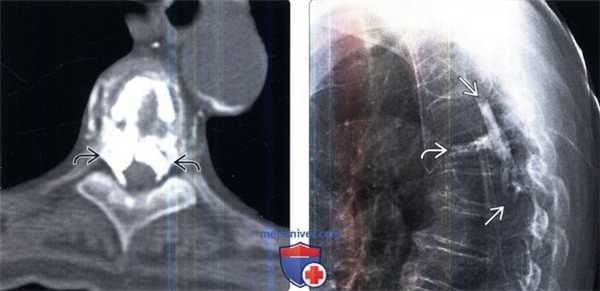

(Слева) Аксиальный КТ-срез: признаки экструзии значительного количества цемента в эпидуральное пространство во время вертебропластики верхнегрудного позвонка по поводу компрессионного перелома, что привело к стенозированию спинномозгового канала.

(Справа) На рентгенограмме этого же пациента также видно, что значительная часть цемента распространяется от сегмента, где выполнялась вертебропластика, вверх и находится в спинномозговом канале.

(Слева) Рентгенография в боковой проекции: признаки экстравазации цемента в межпозвонковый диск после вертебропластики по поводу компрессионного перелома позвонка.

(Справа) На рентгенограмме органов грудной клетки в прямой проекции в верхней доли правого легкого визуализируются извитые плотные тени, представляющие собой цементные эмболы у пациента, которому выполнена вертебропластика нескольких позвонков.